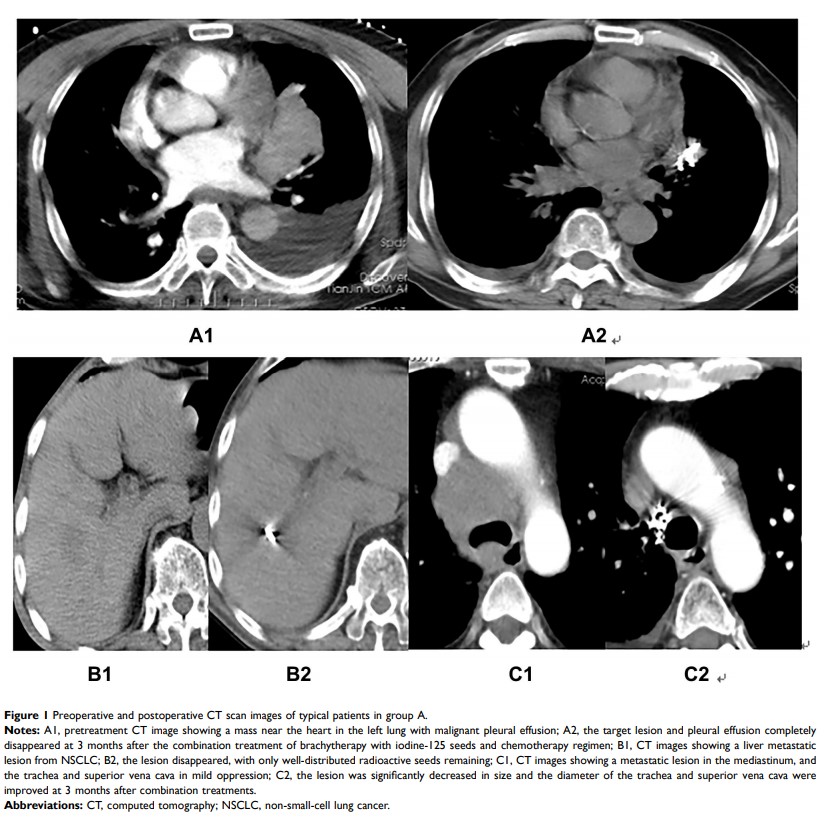

近距离放射疗法与碘 125 种子联合全身化疗与仅采用全身化疗治疗伴颅外寡转移瘤非小细胞肺癌的对比